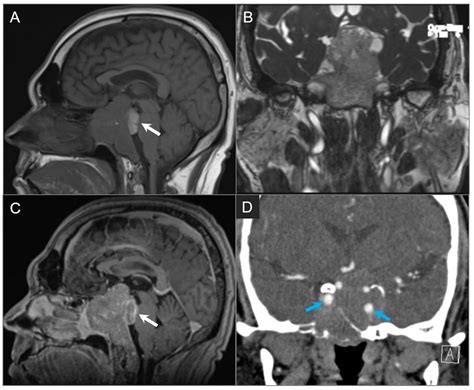

To confirm the presence of a tumor, specialists typically employ a variety of advanced imaging techniques. A standard physical examination is often followed by specialized diagnostic tests to map the extent of the tumor:

MRI (Magnetic Resonance Imaging) Provides high-resolution images of soft tissues, nerves, and the brain.

CT Scan (Computed Tomography) Highly effective at highlighting bony structures and identifying tumor-related bone erosion.